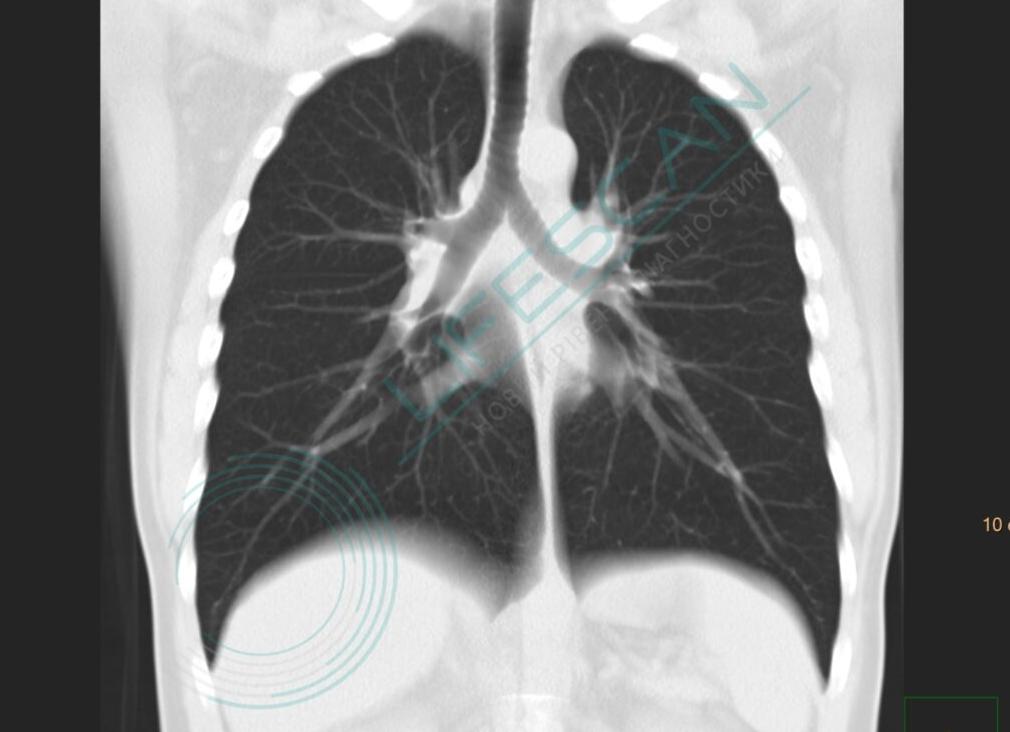

Рис. Нормальная анатомия легких и бронхиального дерева (легочное окно)

1 —Т рахея

2 — Правый главный бронх

3 — Бронх верхней доли правого легкого

4 — Промежуточный бронх

5 — Бронх средней доли

6 —Бронх нижней доли правого легкого

7 —Левый главный бронх

8 — Бронх верхней доли левого легкого

9 —Бронх нижней доли левого легкого

10 — Верхняя доля правого легкого

11 — Средняя доля правого легкого

12 — Нижняя доля правого легкого

13 — Верхняя доля левого легкого

14 — Нижняя доля левого легкого

ПБ-1. Верхушечный сегментарный бронх верхней доли правого легкого

ПБ-2. Задний сегментарный бронх верхней доли правого легкого

ПБ-3. Передний сегментарный бронх верхней доли правого легкого

ПБ-4. Медиальный сегментарный бронх средней доли правого легкого

ПБ-5. Латеральный сегментарный бронх средней доли правого легкого

ПБ-6. Верхушечный сегментарный бронх нижней доли правого легкого

ПБ-7. Медиальный сегментарный бронх нижней доли правого легкого

ПБ-8. Передний сегментарный бронх нижней доли правого легкого

ПБ-9. Наружный сегментарный бронх нижней доли правого легкого

ПБ-10. Задний сегментарный бронх нижней доли правого легкого

ЛБ-1. Верхушечный сегментарный бронх верхней доли левого легкого

ЛБ-2. Задний сегментарный бронх верхней доли левого легкого

ЛБ-(1,2). Верхушечно-задний сегментарный бронх верхней доли левого легкого ЛБ-3. Передний сегментарный бронх верхней доли левого легкого

ЛБ-4. Верхний сегментарный бронх верхней доли левого легкого

ЛБ-яз. Язычковый сегментарный бронх верхней доли левого легкого

ЛБ-5. Нижний сегментарный бронх верхней доли левого легкого

ЛБ-6. Верхушечный сегментарный бронх нижней доли левого легкого

ЛБ-8. Передний сегментарный бронх нижней доли левого легкого

ЛБ-9. Наружный сегментарный бронх нижней доли левого легкого

ЛБ-10. Задний сегментарный бронх нижней доли левого легкого